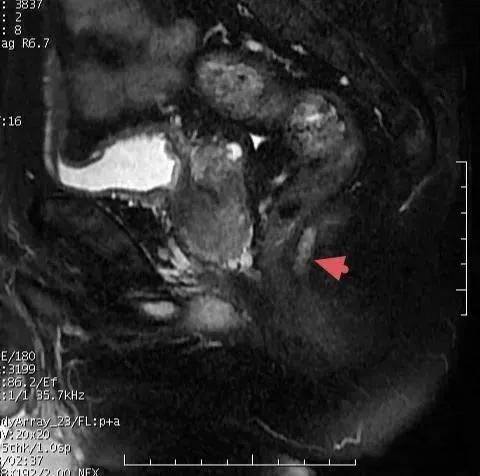

肛瘘磁共振成像

肛瘘是一种常见的肛肠疾病,其治疗难度大、复发率高,一直是困扰外科医生的难题。近年来,随着医学影像技术的发展,磁共振成像(MRI)在肛瘘诊断中的应用越来越广泛,为提高手术成功率和减少复发提供了有力支持。

3. 扫描序列:常用的扫描序列包括T2加权成像(T2WI)、T2脂肪抑制序列(T2WI-FS)、扩散加权成像(DWI)和动态增强扫描(LAVA)。这些序列可以全面评估肛瘘的形态、范围和强化特征。

1. 明确瘘管类型:根据Parks分型,肛瘘可分为括约肌间型、经括约肌型、括约肌上型和括约肌外型。不同类型的肛瘘,其处理方式也不同,因此术前必须明确瘘管与肛管括约肌的关系。

2. 确定内口位置:MRI可以准确识别和定位瘘管的内部和外部开口,这对于手术设计和内口清除至关重要。

3. 评估病变范围:MRI可以清晰显示肛周脓肿、瘘管分支及与肛管肌肉的位置关系,为手术方案的制定提供可靠依据。